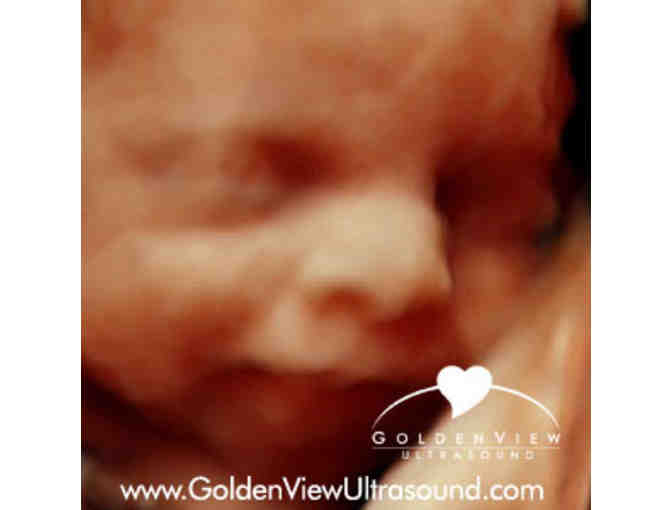

3D/4D with HDLive (5D) Ultrasound (including images) from Goldenview Ultrasound

Winner will receive an Ultrasound Session (images included) with 3D/4D and HDlive (5D) Gender determination (upon request) from Goldenview Ultrasound.

Embrace your pregnancy! Recommended between 20 - 36 weeks.

- (4) 3D/HDlive thermal prints

- (2) 4 x6 glossy 3D/HD color photos

- All still images delivered digitally to your email for easy download and sharing!